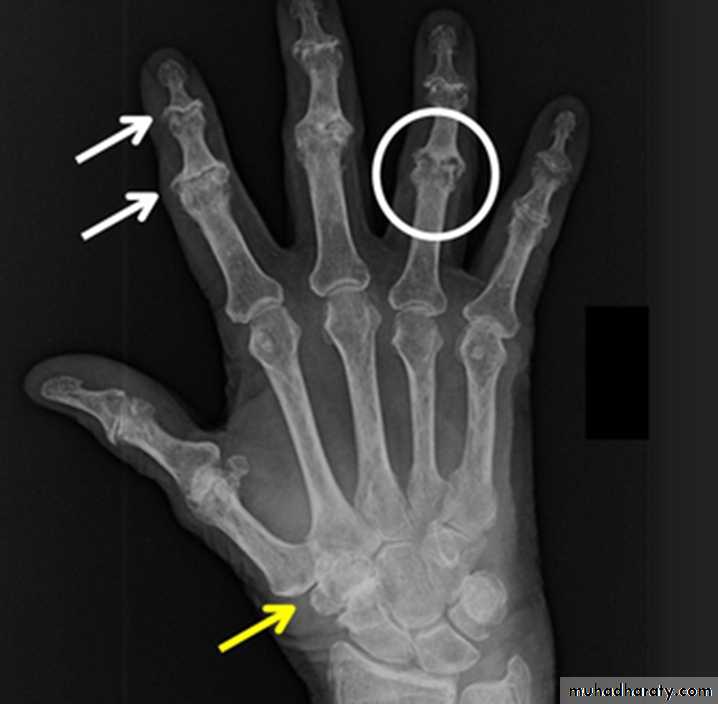

GOUT

Heterogeneous group of entities characterized by recurrent attacks of arthritis secondary to deposition of sodium urate crystals in and around joints.

*90% of patients are male

*Causes due to either Uric acid overproduction, 10% or underexcretion, 90%.

Radiographic features:

Lower extremity > upper extremity; small joints > large joints

* First MTP is most common site

* Marginal, peri articular erosions: overhanging edge

* Erosions may have sclerotic borders

* Joint space is preserved

* Soft tissue and bursa deposition

Tophi: juxtaarticular, helix of ear

Bursitis: olecranon, prepatellar

* Erosions and tophi only seen in longstanding disease

* Tophi calcification, 50%

*Chondrocalcinosis